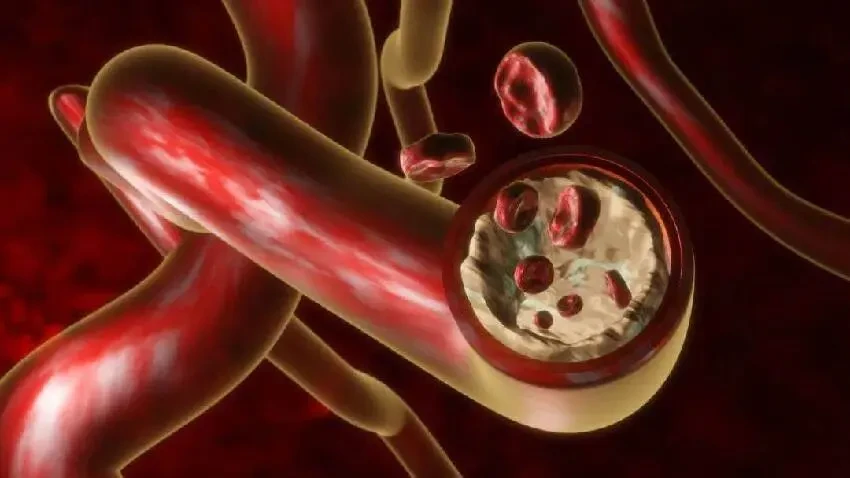

要是血管出現異常膨出,就好比路上突然冒出個大坑,車輛行駛到這兒就得減速、繞行,血液也容易在這些地方形成血栓,進而引發嚴重後果。

一旦血管壁出現異常隆起,這可是血管病變的信號,比如動脈粥樣硬化斑塊的形成。

這些斑塊就如同河道里的淤泥,越積越多,最終堵塞河道。

當體檢報告中的總膽固醇>5.18 mmol/L 且 LDL - C>3.37 mmol/L 時,需警惕動脈粥樣硬化風險,建議結合頸動脈超聲綜合評估。

這可不是簡單的數字超標,背後隱藏的是血管健康的危機,必須引起重視。